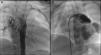

Cardiac catheterization confirmed the existence of collaterals originating from the supra-aortic trunks, the absence of central pulmonary arteries, and left juxtaposition of the atrial appendages (Figure 2). Computed tomography angiography revealed three major aortopulmonary collateral arteries (MAPCAs), one of which originated from the upper portion of the aortic arch, with severe stenosis at its origin and dilatation more proximally. It also showed absence of the pulmonary arteries, a 25-mm interventricular communication, and normal drainage of the pulmonary veins into the left atrium (Figure 3).